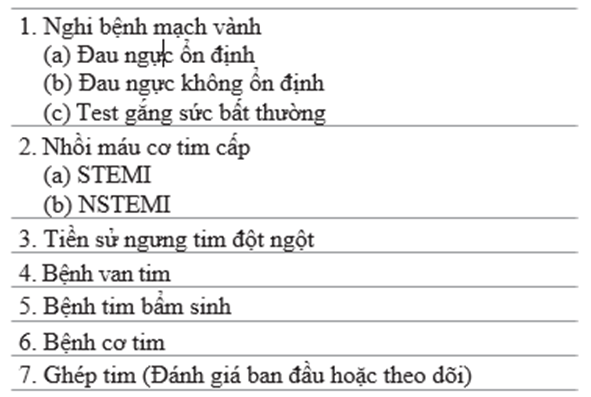

3. Chỉ định chính đặt thông tim ở người lớn là xác định giải phẫu mạch vành và mức độ hẹp của mạch vành. Thủ thuật có thể theo chương trình hoặc cấp cứu [5]. Table 71.2 tóm tắt chỉ định chính của chụp mạch vành. Không có chống chỉ định tuyệt đối với đặt thông tim. Table 71.3 tóm tắt các chống chỉ định tương đối

Table 71.2 chỉ định thông tim